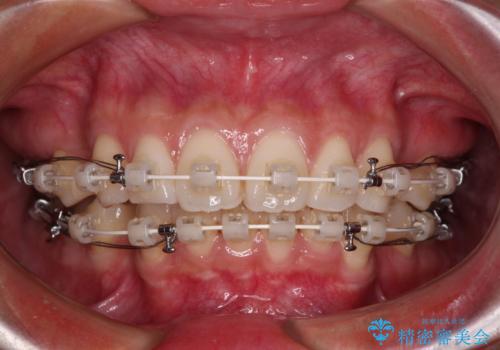

- 矯正装置

- 審美装置

- 飛び出した前歯を気にして来院された患者様です。

口元を引っ込めるために上下左右の第一小臼歯4本を抜歯することとしました。

結婚式を行う予定があるとのことで、表側のワイヤー装置で、速やかに治療を終えられるようにしました。